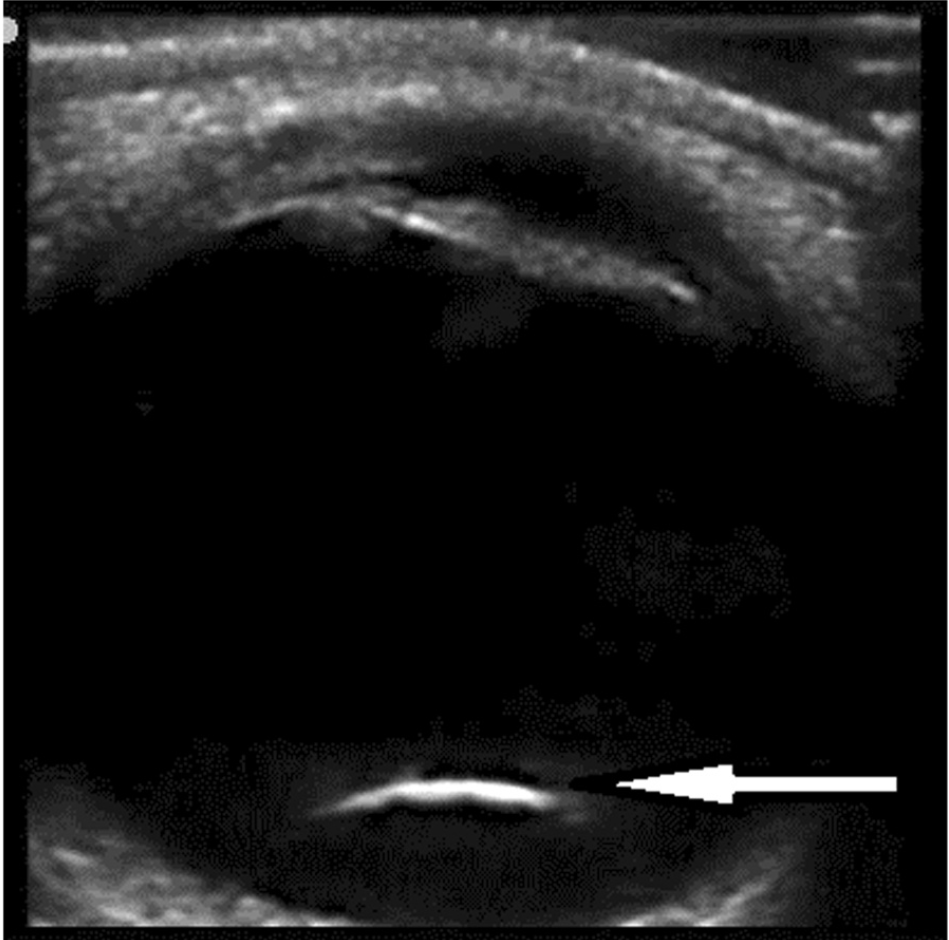

・眼球超音波は網膜剥離や後方への水晶体(レンズ)脱臼の診断に役立つ可能性がある

(Int J Emerg Med. 2015 May 27;8:16.)

ちなみに、水晶体後方脱臼は以下のように見えます。